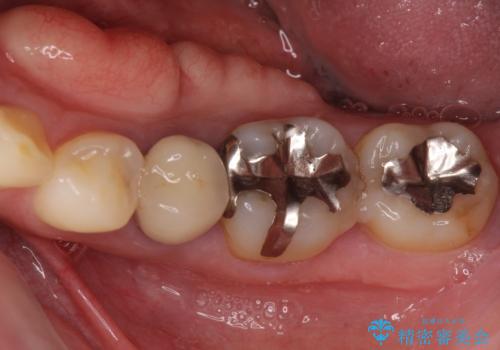

部分矯正を行った後にインプラント埋入と手前の歯の根管治療を行い、その後補綴治療を行うこととしました。

治療途中より、上の歯や反対側の銀歯、上顎前歯の色合いや下顎前歯のデコボコが気になってきたため、全てを治療することとしました。

仕事が多忙な方で、来院間隔が開いてしまうことが多く、治療期間はかかりましたが、来院回数は最小限で終えることができました。